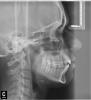

oxpod Опубликовано 2 мая, 2012 Поделиться Опубликовано 2 мая, 2012 (изменено) Здравствуйте, нужна помощь разобраться в ходе лечения.. Проблема такая: самое главное что меня беспокоит - это гипертонус мышц челюсти, рук и ног (примерно 2 года). С детства я дышала ртом, рот был постоянно открыт, сформировался открытый прикус. Позже я научилась насильно держать рот закрытым. Также всю свою жизнь я скриплю зубами во сне. Недавно заметила (месяца три назад), что щелкает правый сустав.Была на консультациях у нескольких ортодонтов, неврологов, сомнолога, лора. Заключение лора - искривление носовой перегородки - буду делать септопластику. Со стороны невролога - гипертонус, присутствует ротовое дыхание, остановок дыхания во сне нет (делали диагностику). Отправили на МРТ шейного отдела, пока не делала. 1 ортодонт. по результатам КТ нижняя чюлюсть находится в положении подвывиха, слева головка НЧ расположена выше на 5 мм, вестибулярнее и мезальнее центра, справа - ниже, дистальнее и кнутри, деструктивные изменения, расстояние до центра - от ветви НЧ слева 105 мм, справа 115 мм. Со стороны шейного отдела - суст. отросток Dens Т2 ротирован против часовой стрелки, наклонен и смещен влево. План лечения : нормализация черепно-челюстной системы- устранение подвывиха НЧ и установка ее в оптимальное равновесие. Применение Тенс-монитора, изготовление окклюзионной каппы Ортотик. Устранение гиперонуса у остеопата, удаление 18 28 38 48, пластика мягких тканей рта, вестибуло- и френуло-пластики для устранения рецессии, горизонтальной резорбции костной ткани альвеолярных отростков. Ортодонтическое лечение - нормализация окклюзии, устранение деформации зубных рядов, пожизненная ретенция, пл-ка с защитой для языка на ночь.Диагноз: нейтральная окклюзия 1 класс по Энглю вертикальная резцовая дизокклюзия правосторонняя, узкий апикальный базис верхней и нижней челюсти макроденти фронтальных и боковых зубов, смещение центральной линии, укороченная уздечка верхней губы и нижней губы, дисфункция мышц языка макроглоссия затрудненное носовое дыхание, нарушение осанки, дисфункция ВНЧС 2. Нашла в нашем городе другую клинику, где применяют Тенс и ортотик, была на консультации у профессора, он сначала отправил меня к лору (где выяснилось искривление перегородки), к неврологу-сомнологу (где выяснилось что дыхание во сне в норме). Сказал что лечение предыдущего ортодонта неправильное, так нельзя начинать лечение без расчета по ТРГ. Отправил меня к своим ортодонтам(их у него в клинике два), предварительно сделав ТРГ, а сам уехал на месяц. Сказал что если по расчету ТРГ у меня прикус завышен, ортотик мне применять нельзя. Первый его ортодонт сказала что нужно удалять восьмерки и ставить брекеты. И сказала что у меня инфантильное глотание. Вторая сказала удалять пятерки и ставить брекеты. Что делать с суставами и гипертонусом мне так и осталось не ясно. Вопрос в том, что хотелось бы знать правильный план лечения, с чего нужно начать, в какой момент подключить остеопата, нужен ли мне тенс монитор и ортотик или нужен другой способ установки челюсти в правильное положение. Как я понимаю брекеты ставить сразу смысла нет, станет еще хуже? Заранее спасибо всем откликнувшимся, фото улыбки прилагаю, второе фото с начала - расслабленное положение рта, первое и второе фото ОПТГ (делала месяц назад) , последнее - в октябре 2011 г. Фото сжала, так как с изначальным размером не прикреплялось.с уважением! Изменено 2 мая, 2012 пользователем oxpod Ссылка на комментарий

Skip Опубликовано 2 мая, 2012 Поделиться Опубликовано 2 мая, 2012 1 ортодонт. по результатам КТ нижняя чюлюсть находится в положении подвывиха, слева головка НЧ расположена выше на 5 мм, вестибулярнее и мезальнее центра, справа - ниже, дистальнее и кнутри, деструктивные изменения, расстояние до центра - от ветви НЧ слева 105 мм, справа 115 мм. Со стороны шейного отдела - суст. отросток Dens Т2 ротирован против часовой стрелки, наклонен и смещен влево.А можно взглянуть непосредственно КТ? Вопрос в том, что хотелось бы знать правильный план лечения, с чего нужно начать, в какой момент подключить остеопата, нужен ли мне тенс монитор и ортотик или нужен другой способ установки челюсти в правильное положение. Как я понимаю брекеты ставить сразу смысла нет, станет еще хуже? Сложно сейчас комментировать предложенный Вам план лечения, т.к. я не услышал диагноза в отношении ВНЧС, а именно с этого нужно начинать. Нейромышечные ортотики хорошо работают только при вправляемом вывихе диска и когда щелчок определяется в пределах 2 см. открытия рта. В отношении междисциплинарного подхода, включающего остеопата, то у меня здесь есть большие сомнения в эффективности, т.к. будет отсутствовать единый синтаксис лечения. Вы узнайте корректно у врачей, где они этому учились и есть ли какие-либо результаты, не стесняйтесь, ведь это Ваше здоровье. На ТРГ можно взглянуть..? Ссылка на комментарий

oxpod Опубликовано 4 мая, 2012 Автор Поделиться Опубликовано 4 мая, 2012 (изменено) А какую проблему имел ввиду невролог, проблему с ВНЧС? Шейный отдел позвоночника не может служить источником проблемы сам по себе. Данный участок является последней территорией, на котором возникают компенсаторные дисфункции в ответ на нижележащие повреждения. Это, как раз, является поводом обратить внимание на область SI (крестцово-подвздошное сочленение) или L4-L5. Мы у себя обычно ставим декомпрессионный аппарат для ВНЧС (ортотик), а мануальный терапевт стабилизирует SI. Здесь визуализируются только костные элемента сустава и часть его кинематики. Проблемы со связками и диском только на МРТ. Неврологу я жаловалась на гипертонус мышц челюсти, рук и ног, она направила на ночную диагностику дыхания, за ночь у меня было 5 (примерно около 10 сек.) апноэ, сказала что это норма, и что будем дальше искать проблему, и направила на МРТ шейного отдела. Кстати боли в шее бывают, когда сижу долго, или в наклоненном состоянии долго Прикрепляю как вы сказали скрин КТ, нужно ли посмотреть какие-то рарезы? Изменено 4 мая, 2012 пользователем oxpod Ссылка на комментарий

Skip Опубликовано 4 мая, 2012 Поделиться Опубликовано 4 мая, 2012 а мне вы написали, что Шейный отдел позвоночника не может служить источником проблемы сам по себе. Не подумайте что я докапываюсь к словам, просто я запуталась... Во-первых, сказанное было адресовано конкретному пациенту с характерной неврологической симптоматикой и не нужно это примерять на себе.Во-вторых, не нужно смешивать мух и котлеты. Говоря о сегментах шейного отдела, я имел ввиду только интракапсулярные проблемы с Вашим ВНЧС, где не существует никакой прямой причинно-следственной связи. Сделайте МРТ, как рекомендует Ваш невропатолог и затем, после его заключения и если возникнут ко мне вопросы, поговорим более предметно. Меня просто немного удивило, отчего сразу МРТ? Вам проводили какие-нибудь диагностические тесты? У Вас была травма шейного отдела? Сколько Вам лет, если не скекрет?Кстати, нестабильность шейного отдела можно расчитать и по боковой ТРГ, убив сразу двух зайцев, для этого существуют соответствующие методики. Скрин КТ хороший, но мне хотелось бы увидеть другой, где определяется, цитирую:по результатам КТ нижняя чюлюсть находится в положении подвывиха, слева головка НЧ расположена выше на 5 мм, вестибулярнее и мезальнее центра, справа - ниже, дистальнее и кнутри, деструктивные изменения, расстояние до центра - от ветви НЧ слева 105 мм, справа 115 мм. Со стороны шейного отдела - суст. отросток Dens Т2 ротирован против часовой стрелки, наклонен и смещен влево....и особенно, то, что выделено жирным шрифтом. Учитывая в анамнезе родовую травму, мне теперь, более менее, понятна природа всех Ваших недугов. И положа руку на сердце хочу дать Вам совет - не тратьте зря время (и средства) на тенс, миомонитор, ортотик и т.п. Ссылка на комментарий